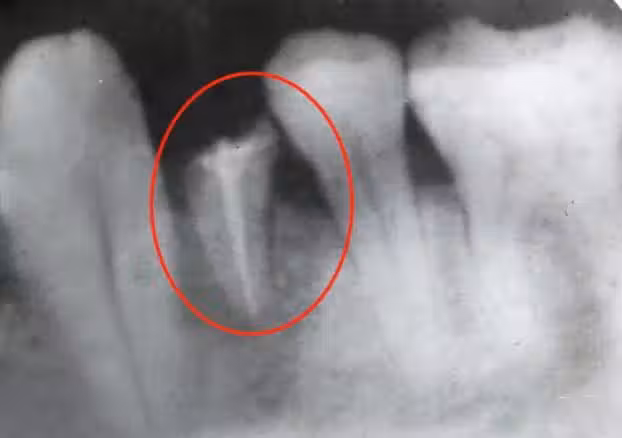

醫生結合症狀和檢測結果,判定張女士患上的就是「乾燥綜合徵」。

乾燥綜合徵

乾燥綜合徵是一種慢性疾病,患者以中老年女性居多。很多人對這個病知之甚少,相信大家都有這樣的疑惑:「口乾舌燥不是很常見的嗎?有那麼嚴重嗎?」